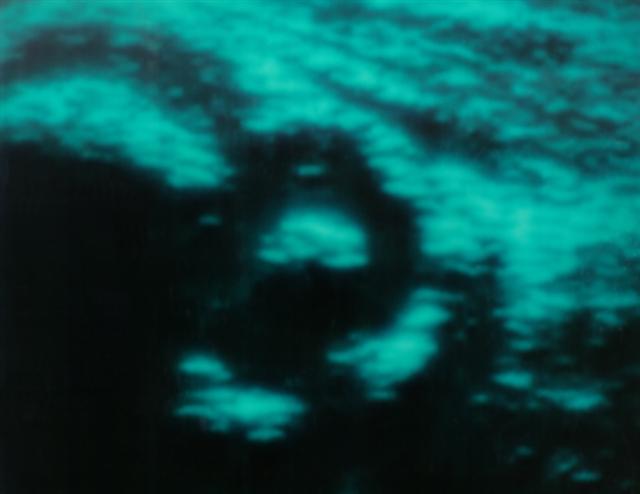

Рис. 7б). Ультрасонограмма тазобедренного сустава с 1 типом строения (подтип А) у ребенка первых месяцев жизни.